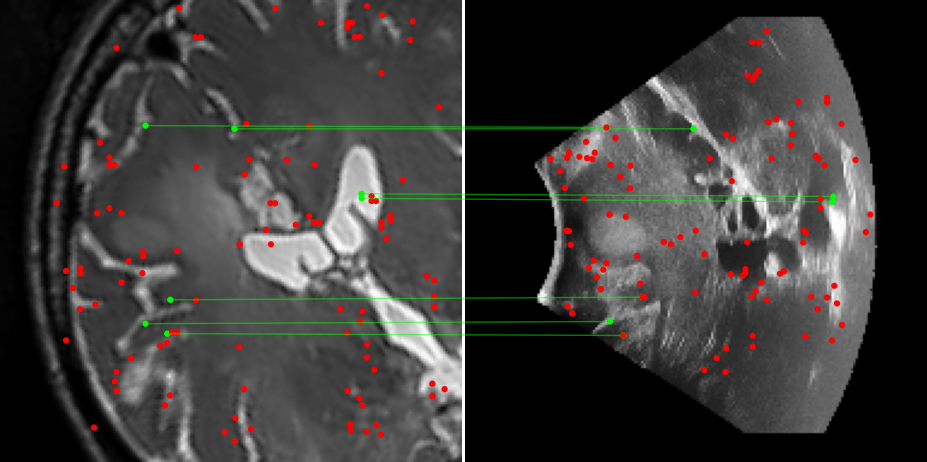

Figure 3: Examples of matching on three cases, one per column (MR on left and US on right). From top to bottom: SIFT+Cosine, MIND+Cosine, SP+Cosine, SP+LG, Ours+LG, Ours+Cosine. Correct matches recovered by each method are shown in green lines and mismatched are shown with a red dot.